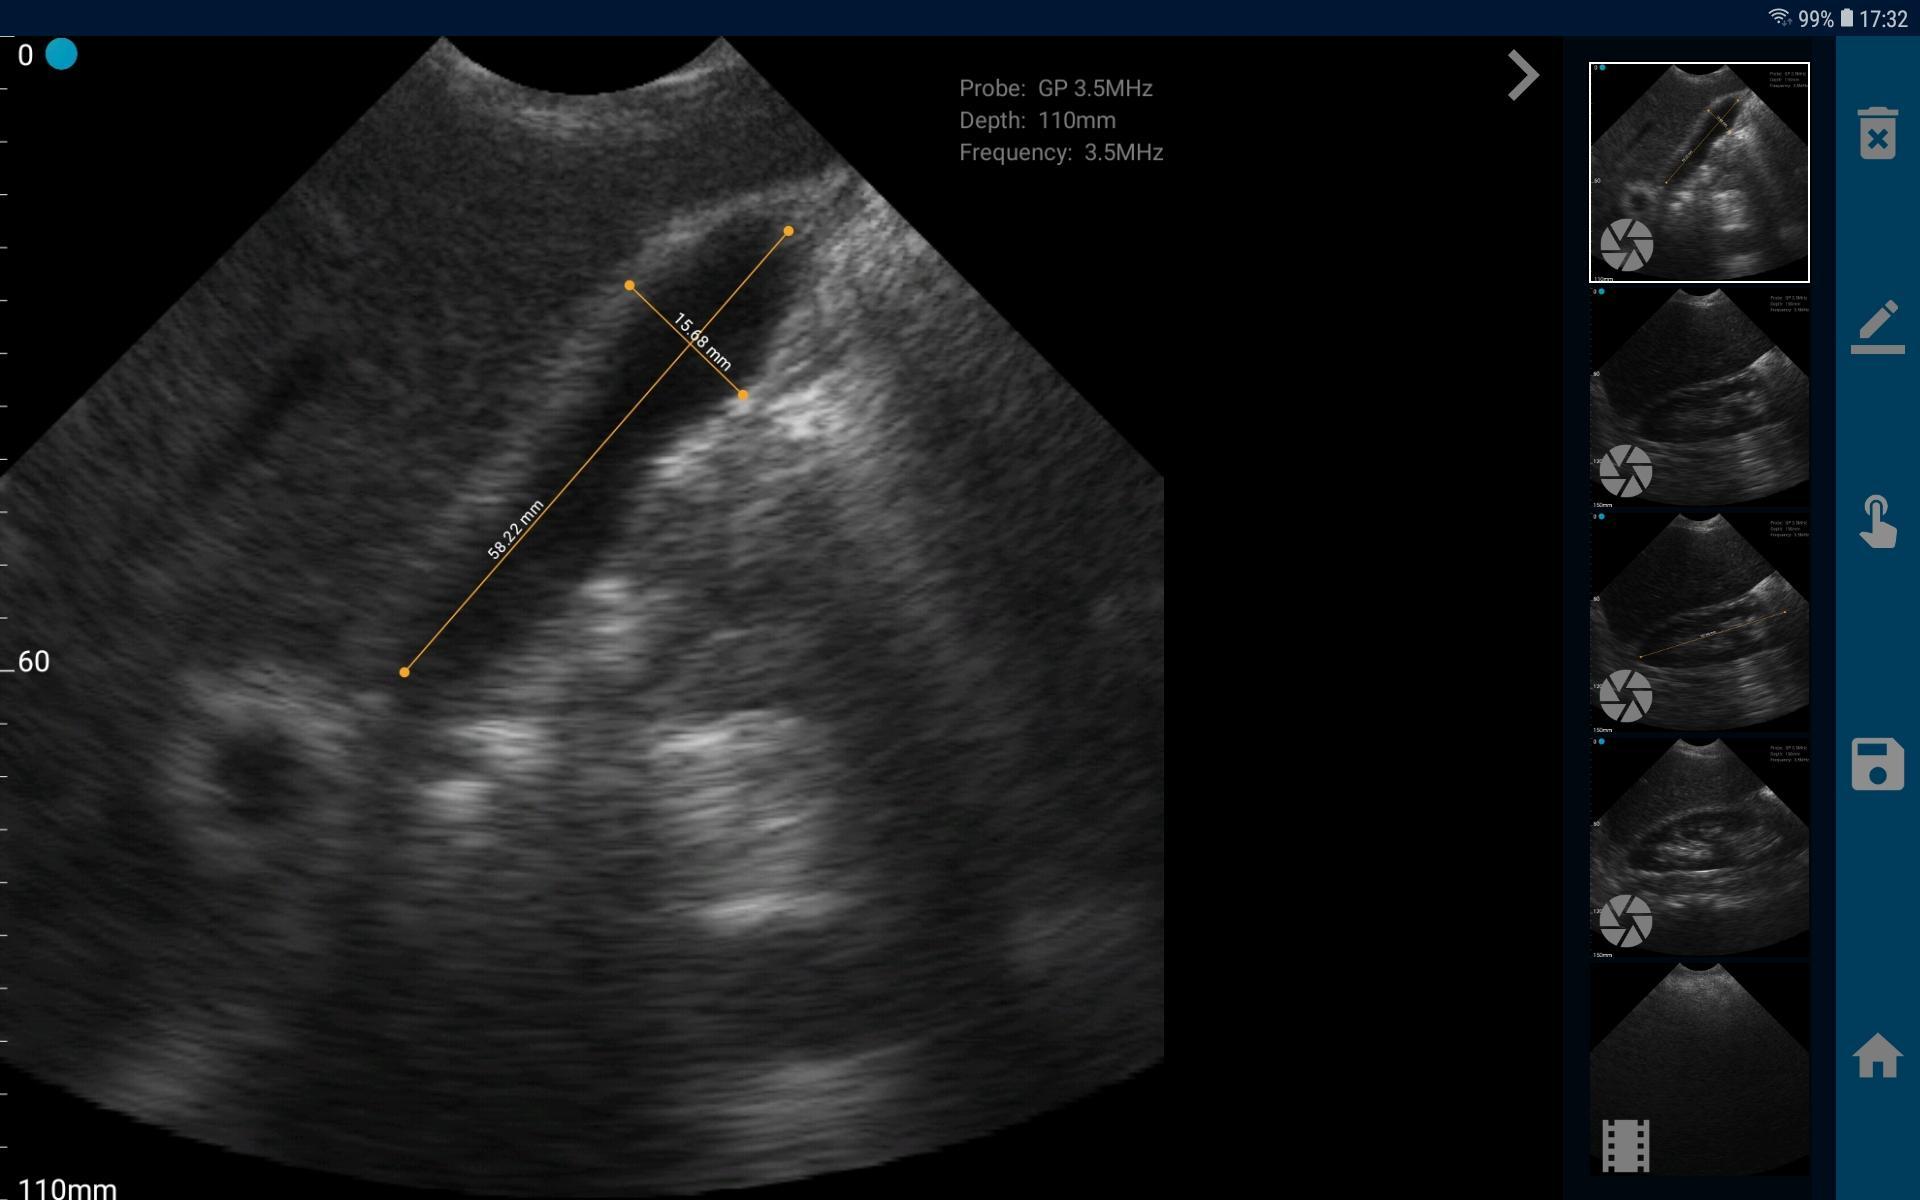

Компания разработала специальное программное обеспечение, которое позволяет врачам использовать дисплей смартфона или планшета для измерения соответствующих анатомических маркеров с точностью до пикселей. Технология имеет множество применений, в частности, система может использоваться для лечения пациентов в полевых условиях и для обеспечения автомобилей "Скорой помощи" диагностическими возможностями ультразвукового устройства, которые могут быть использованы по пути в больницу.

Запатентованная программная платформа VistaScan превращает мобильный телефон или планшет в аппарат УЗИ. В отличие от других портативных ультразвуковых технологий, здесь не требуется много времени для подготовки и научиться использовать эту простую для пользователя платформу можно за считанные минуты. Компания при этом предлагает различные легкие и эргономичные датчики, которые могут обеспечить многочасовое сканирования без подзарядки. По утверждению компании-производителя, пользователь системы VistaScan получает превосходное качество изображения, причем по цене более чем в 10 раз более низкой, чем обходится традиционный ультразвуковой аппарат на тележке.